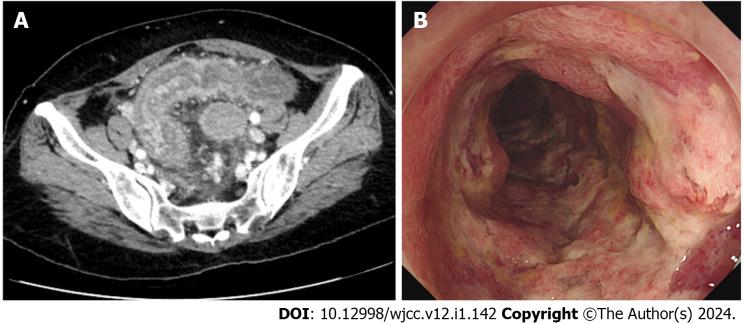

We present the case of a 68-year-old female patient who underwent laparoscopic left hemicolectomy for transverse colon cancer 3 years ago. Postoperatively, follow-up included an annual colonoscopy and abdominal computed tomography (CT) at a local clinic. However, progressive erythema and edema of the sigmoid colon were observed 1 year postoperatively. Upon admission to our hospital, she complained of abdominal pain and diarrhea. Abdominal CT showed thickening of the sigmoid colon walls, and colonoscopy revealed erythema, edema, and multiple ulcers with exudate in the sigmoid colon. CT angiography showed engorgement of the sigmoid vasa recta without any vascular abnormalities. The diagnosis was congestive ischemic colitis, and we treated the patient with anti-inflammatory agents. After 2 mo of glucocorticoid therapy (20 mg once daily) and 7 mo of 5-aminosalicylate therapy (1 g twice daily), the ulcers completely healed. She has not experienced any recurrence for 2 years.

我们报告一例68岁女性患者,她3年前因横结肠癌接受了腹腔镜左半结肠切除术。术后,在当地诊所进行的随访包括每年一次的结肠镜检查和腹部计算机断层扫描(CT)。然而,术后1年观察到乙状结肠出现进行性红斑和水肿。入院时,她主诉腹痛和腹泻。腹部CT显示乙状结肠壁增厚,结肠镜检查显示乙状结肠有红斑、水肿和多处伴有渗出物的溃疡。CT血管造影显示乙状结肠直血管充血,无任何血管异常。诊断为充血性缺血性结肠炎,我们用抗炎药对患者进行了治疗。经过2个月的糖皮质激素治疗(每日一次,每次20mg)和7个月的5-氨基水杨酸治疗(每日两次,每次1g),溃疡完全愈合。她2年来未出现任何复发。